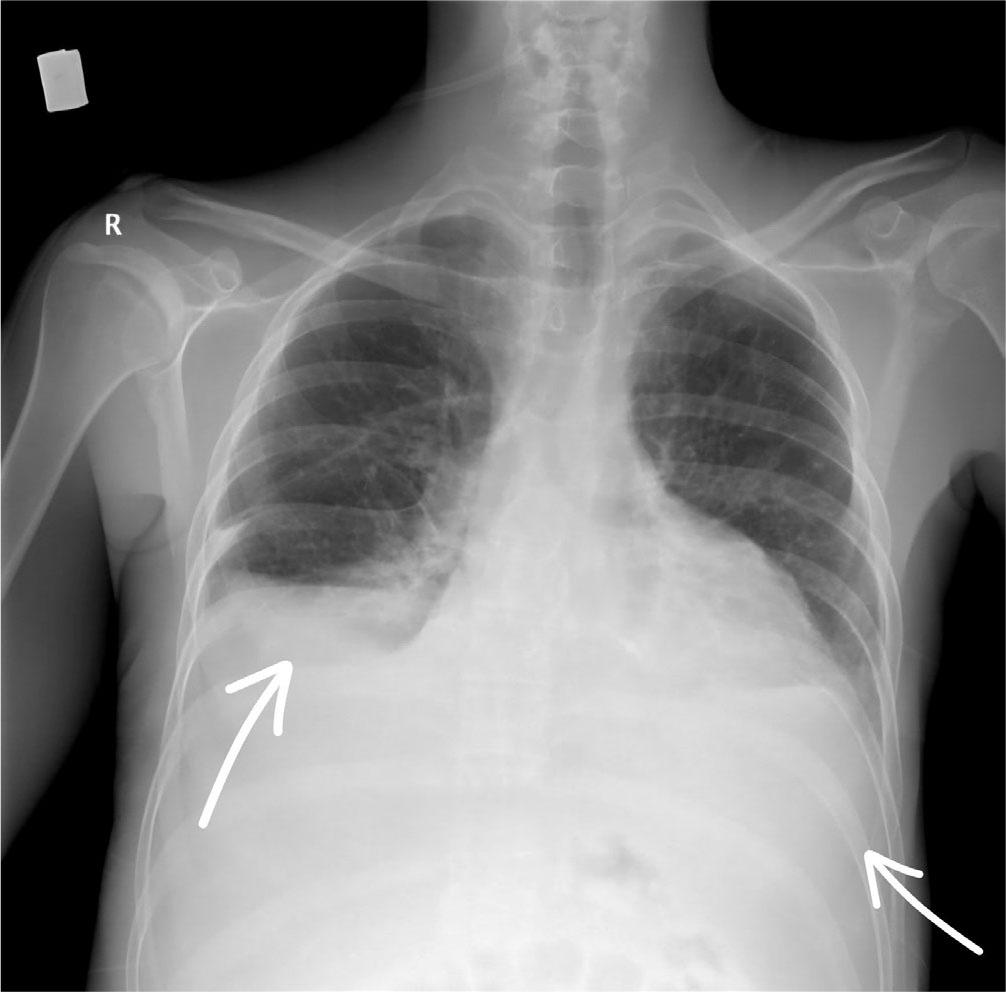

After seven days of antibiotic treatment with Meropenem and Linezolid, the infectious syndrome partially subsided (leucocytes 20×103/μL, neutrophils 17×103/μL, C-Reactive Protein 70 mg/L, fever subsided). However, the patient’s clinical condition deteriorated, with marked dyspnea, tachypnea, oxygen saturation of 80% with non-rebreather mask, hemodynamic instability, heart rate of 125/min and blood pressure of 80/60 mmHg (qSOFA score of 2 points). A central jugular venous catheter was placed, and inotropic and vasopressor support with Noradrenaline 0,05 μg/kg/min up to 0,1 μg/kg/min (Amdipharm, Ireland) was initiated. Analyzing the cause of hypotension, we interpreted the drop in blood pressure as being more in the context of septic shock than cardiogenic shock. Given that septic shock is accompanied by peripheral vasodilation, we chose a positive inotropic agent with a vasoconstrictor effect. Furthermore, we considered that it was unlikely to be cardiogenic shock, as the patient’s echocardiography showed a left ventricular ejection fraction of 45%, which was sufficient to maintain cardiac output at rest. Thoracentesis and paracentesis were performed for therapeutic and diagnostic purposes, with evacuation of 1300 mL of clear serous pleural fluid and 4000 mL of ascites. Bacteriological tests were performed on both pleural and ascitic fluid, but no bacterial growth was detected. After the procedure, oxygen saturation increased to 95% with a non-rebreather mask, and the post-thoracentesis chest X-ray ruled out the presence of new congestive foci and pneumothorax (Figure 4). Given the evacuation of 4000 mL of ascites in a patient with albuminemia of 3g/dL and acute renal failure, we considered the administration of albumin to be inappropriate.

Chest X-ray after bilateral thoracentesis – no condensation foci, no signs of pneumothorax